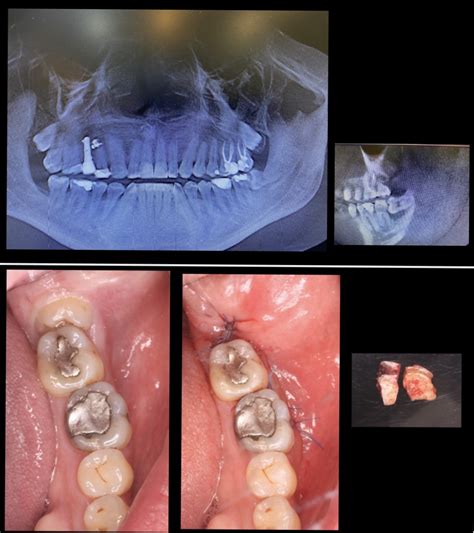

¿Qué ocurre tras una extracción dental?

Después de extraer una muela, el cuerpo inicia inmediatamente el proceso de curación. Se forma un coágulo de sangre en el sitio de la extracción, que es esencial para la cicatrización.

Cuando se extrae un diente, un coágulo de sangre se forma naturalmente sobre el área donde el diente se sentó previamente.

Complicaciones y señales de alerta

Aunque la mayoría de las extracciones dentales cicatrizan sin problemas, es importante estar atento a posibles complicaciones.

- Alveolitis seca: En los casos en el cual hay mucho dolor y que empieza normalmente a las 24 horas después de la intervención quirúrgica, puede deberse a una infección conocida como alveolitis seca y deberás consultar lo antes posible con tu dentista.

- Necrosis del tejido: La complicación más importante que puede darse es que el tejido se necrose por falta de vascularización. Es decir, no recibir el suficiente riego sanguíneo.